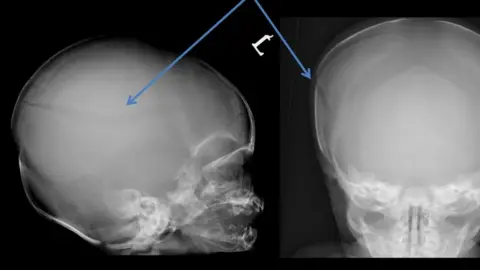

Stanley Davis died in hospital in March 2017 from a broken skull after previously sustaining 41 fractures.

Det Ch Insp Fiona Bitters said: "Stanley was found to have sustained 32 fractures to his ribs, nine fractures to the bones in his arms and legs, and an 8cm (3in) skull fracture.